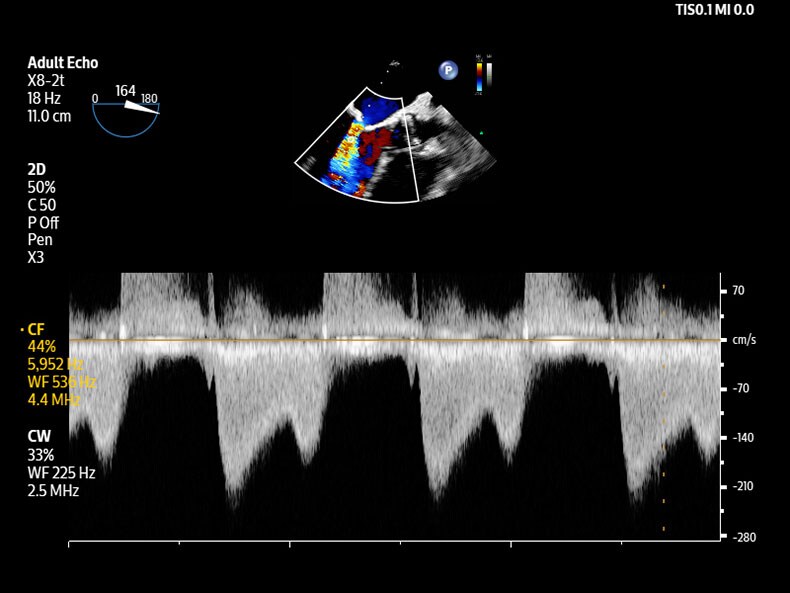

Madrid, 01 de octubre de 2025 – Royal Philips, compañía líder en tecnología sanitaria, ha anunciado el lanzamiento global de su nuevo sistema de ecografía Flash Ultrasound System 5100 POC, un equipo pionero especialmente diseñado para su uso a pie de cama o allí donde lo requiera el paciente. Este sistema responde a las necesidades de anestesia, cuidados críticos, urgencias y diagnóstico musculoesquelético, y da un paso adelante al incorporarse en las áreas de dermatología y medicina deportiva, integrando sondas lineales de alta frecuencia que permiten explorar con mayor detalle estructuras superficiales de la piel, músculos y tendones, ofreciendo imágenes de alta definición que se traducen en diagnósticos más precisos y seguros. Con la reconocida experiencia de Philips en cardiología y ecografía general, el Flash 5100 POC ofrece una claridad de imagen sobresaliente, automatización inteligente y controles táctiles intuitivos en un formato realmente portátil, permitiendo decisiones rápidas y seguras en cualquier entorno clínico, independientemente del nivel de experiencia del usuario. Su flujo de trabajo orientado al punto de atención ayuda a realizar y documentar exámenes en tiempo real, eliminando esperas por órdenes formales y adaptándose a la presión de áreas como urgencias, UCI y unidades de trauma.

Philips estima que sus sistemas de ecografía a pie de cama permiten la realización de 52 millones de procedimientos cada año, contribuyendo al diagnóstico y tratamiento de 41 millones de pacientes en todo el mundo. El lanzamiento del Flash 5100 POC es un paso clave para dar respuesta a la creciente demanda de tecnología de ultrasonidos portable y de alto rendimiento junto al paciente. Entre sus innovaciones destacan software preparado para el futuro, la compatibilidad con transductores de distintas plataformas – como el galardonado mL26-8, especialmente indicado para musculoesquelético – y la integración en el ecosistema Philips junto a Lumify y Compact 5000 Series, permitiendo escalar y estandarizar la atención de manera eficiente y coste-efectiva.